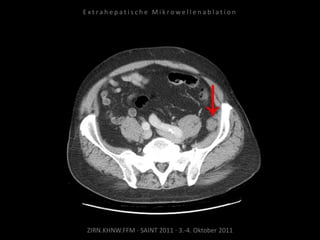

Metastase kaudal der linken Niere:

Apikal 2 Nadelpositionen.

Kaudal 1 Nadelposition.

Erneute Ablation von 2 peritonealen

Metastasen am 09.09.2010.